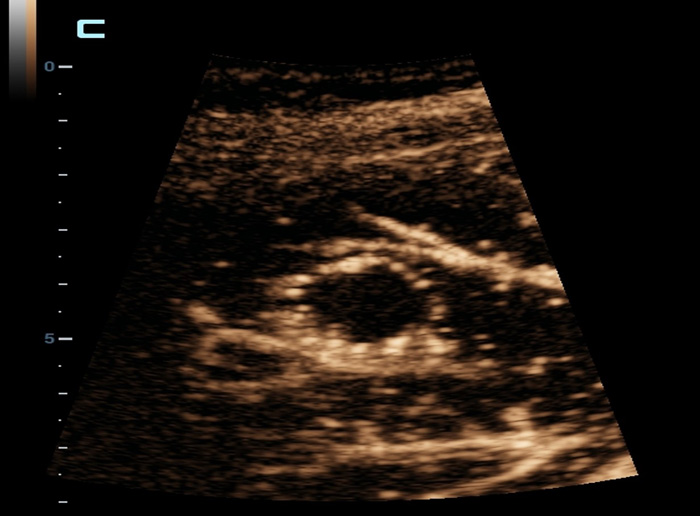

Strumenti di analisi multiparametrica M-Reference

M-Ref. C&E

M-Ref. C&E tumore maligno al seno

M-Ref. C&E supporta la visualizzazione del contrasto e della STE in un unico piano per una valutazione comparativa della perfusione e dell'elasticitĂ .